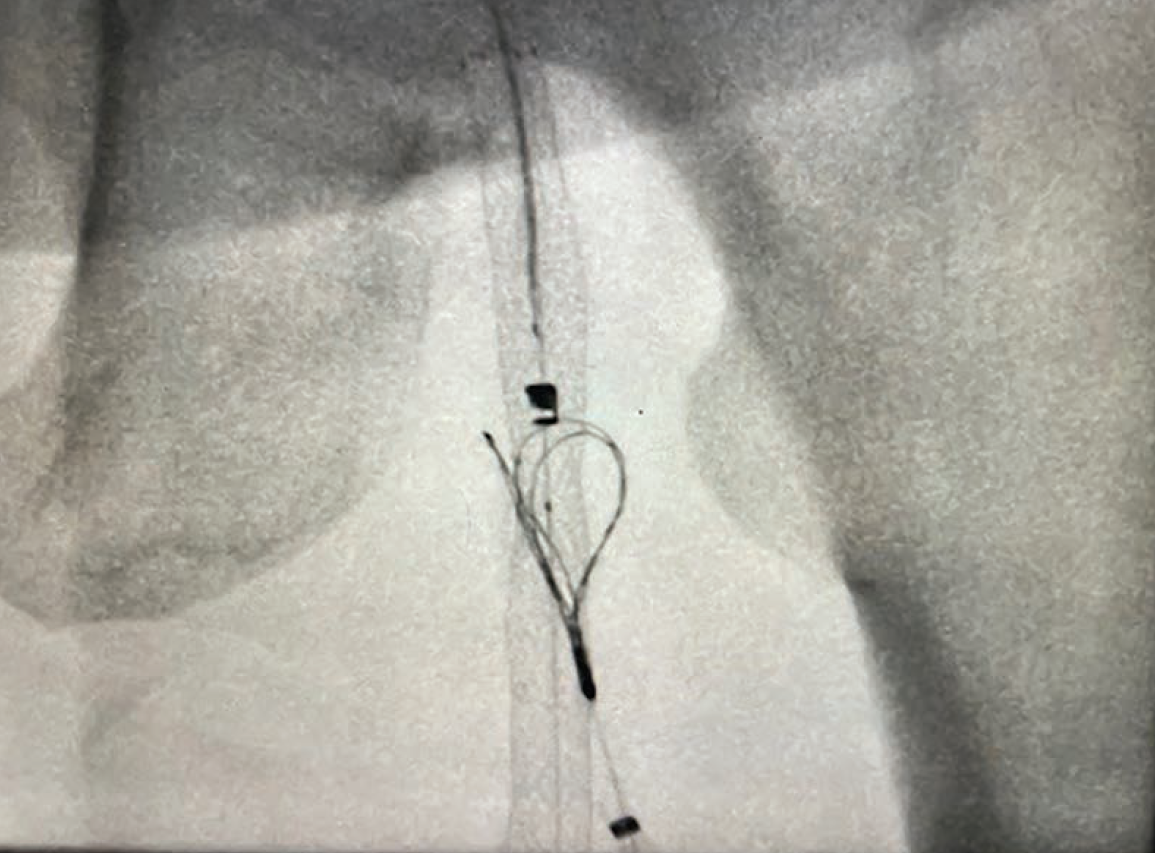

The procedure on her left leg took approximately 120 minutes, and she did exceptionally well (Figures 1A-D). The revascularization was successful and her left leg healed as expected. About a month later, she returned to us and, to our surprise, asked if we could perform the same procedure on her right leg. She was impressed by how much easier the percutaneous bypass was compared to her previous experience with open surgical bypass, which had been a challenging and difficult course for her.

We proceeded with the procedure on her right leg, and once again, the results were excellent. This case serves as a great example of how PTAB with the DETOUR System can effectively treat bilateral SFA disease, even when the severity of disease differs between the legs. One leg was treated for critical limb ischemia, while the contralateral leg was treated for claudication. Her follow-up appointments have shown remarkable results, with the patient very satisfied with her outcome, and she continues to do well.